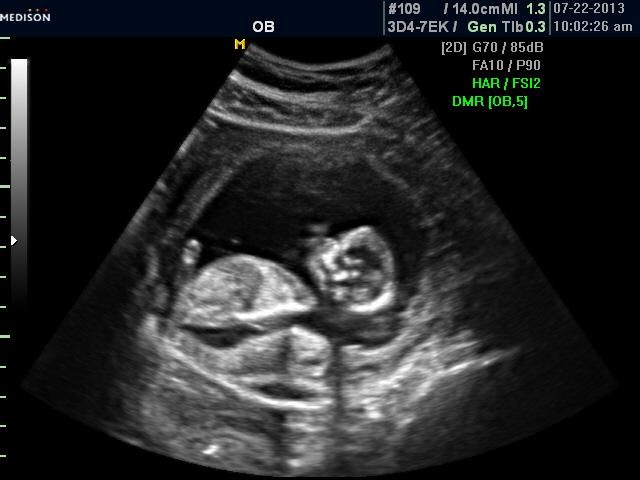

My little sister just had her u/s today..she is 13 weeks 6 days. Any guesses would be appreciated! Thank you all!Attachment 12505Attachment 12506Attachment 12507Attachment 12508

I *think* there is a boyish nub on the second picture. Only prob is that baby is pretty arched. I would go 60-40 boy.

guessing girl based on the third photo :)